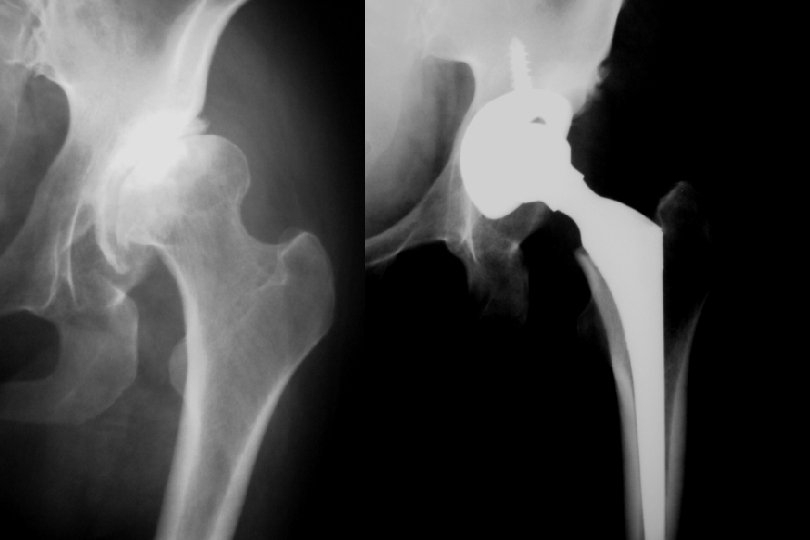

Adult • Artrodez !!! • Total Eklem Replasmanı • Genç ve aktif yaştalar • İyileştirilmiş malzemeler kullanılmalı • Hasta çok detaylı bilgilendirilmeli